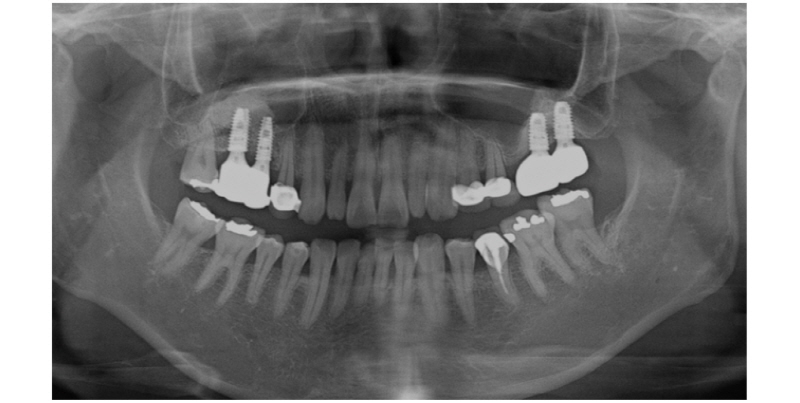

만 52세 여성 환자는 양측 상악 구치부 임플란트 주소로 내원하였다. 초진 18개월 전 #17,16,26,27 발거한 병력 있으며, 전신적으로는 잘 조절되는 고혈압이 있었다. 좌측 상악동 부위 측방 접근법을 통해 상악동거상술 시행했으며, 10개월 후 임플란트 식립하여 3년 이상 안정적으로 유지되고 있다.

상악 우측 부위 상악동 거상술 역시 측방 접근법을 통하여 시행하였으며, 상악동 점막 거상 시 직경 1 mm가량의 천공 발생하여 흡수성 콜라겐 차단막(CollaTape®, Zimmer, USA)으로 봉합하였다. 수술 후 약 4일 간격으로 환부 소독하였으나 지속적인 통증 및 부종, 열감으로 인해 2주 후 골이식재 제거하였다. 이후 증상 사라졌으며, 1년간의 치유 기간을 가졌다 (Fig. 4).

감염 부위 제거 1년 후, 우측 상악 구치부 상악동 거상술을 위해 다시 측방 접근법을 이용하였다. 골이식재 동반한 상악동거상술 후 측벽창은 흡수성 콜라겐 차단막 이용하여 마무리하였다 (Fig. 5). 상악동거상술 4개월 후 임플란트 1차 수술하였으며, 신흥 인터내셔널의 Luna 시스템 이용하였고, 고정체 식립 시 20 Ncm으로 고정하였다. 1차 수술에서 조직 검사 및 지대주 연결 함께 시행하였다. 임플란트 수술 5개월 후 최종 보철물 접착하였으며, 수술 후 10개월이 지난 현재까지 안정적으로 잘 유지되고 있다 (Fig. 6).

증례 2는 상악동거상술 후 감염으로 인해 제거된 부위에서의 재수술에 대한 내용이다. 감염으로 인한 골이식재 제거 후 1년간의 긴 치유기간 후 재수술 시 안정적인 판막 거상 및 치유 기전을 보였으며, 이종골이식재 역시 감염 없이 잘 유지되었다. 현재 최종 보철물 접착 후 5개월간의 경과관찰을 가졌으며, 이에 대한 장기적인 예후 평가가 필요할 것이다.

1차 수술 후 2주간 염증 증상이 나타났으며, 해당 부위 감염된 골이식재를 제거하였다. 1년의 치유기간을 가진 후 재수술 시 측벽창의 골결손이 남아있는 것을 관찰할 수 있었는데, 제거술까지의 시기가 지연되었다면 골결손부의 크기가 커졌을 것이라 예상된다. 상악동거상술 후 감염 발생 시 빠른 제거 및 후처치가 필요할 것이며, 재수술을 위한 치유기간에 대한 연구는 더 필요할 것이다.